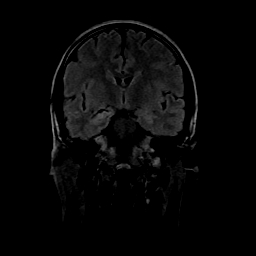

女性,47岁。mri号03027,外伤致头痛9天,抽搐一天,原无类似病史。

dwi及矢状位无明显异常,所以没发。

颞叶前部萎缩,海马萎缩,t2wi海马高信号,支持海马硬化。